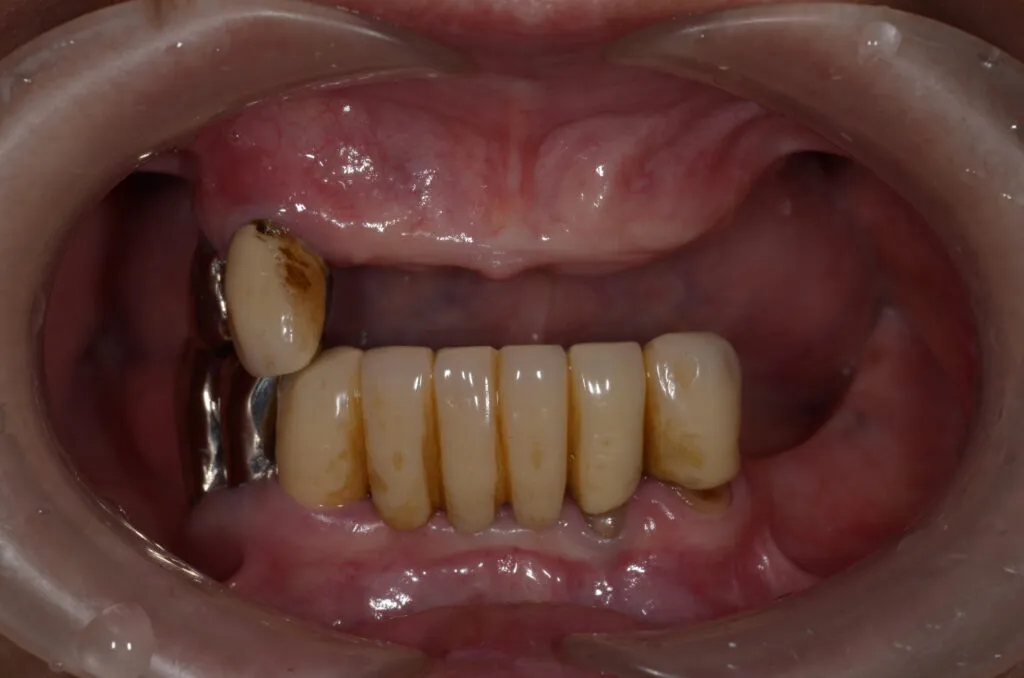

こちらの患者様の場合

【期間】2ヶ月

【費用】¥350,000~¥400,000/片顎(税抜)

【デメリット】精密に製作するため、保険の入れ歯よりも回数・費用がかかります。

上記写真は当院で上下総義歯を作製した患者さんです